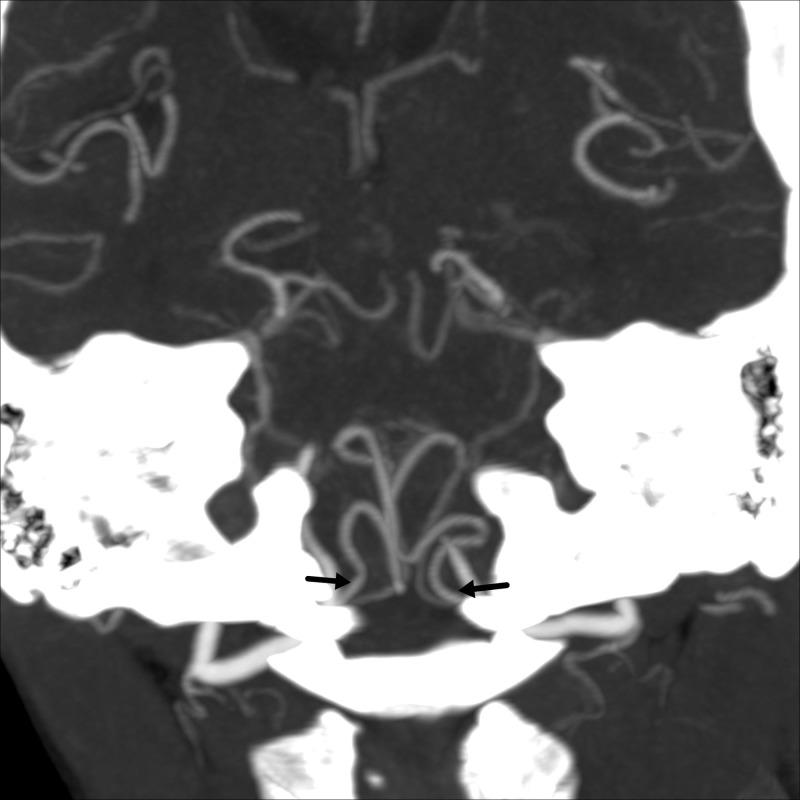

Cocaine Induced Bilateral Posterior Inferior Cerebellar Artery and Hippocampal Infarction.

Cocaine is one of the most commonly abused recreational drugs, second only to marijuana. It blocks the reuptake of neurotransmitters such as norepinephrine and dopamine, that leads to persistent post-synaptic stimulation responsible for its excitatory effects. Cocaine-related strokes, both ischemic and hemorrhagic, have been well described in the literature and cerebral vasospasm is hypothesized as one of the major mechanisms responsible for the presentation. Although cases of posterior circulation infarction were previously reported, we herein report a rare presentation of a cocaine-induced bilateral posterior inferior cerebellar artery and hippocampal infarction in a middle-aged female.